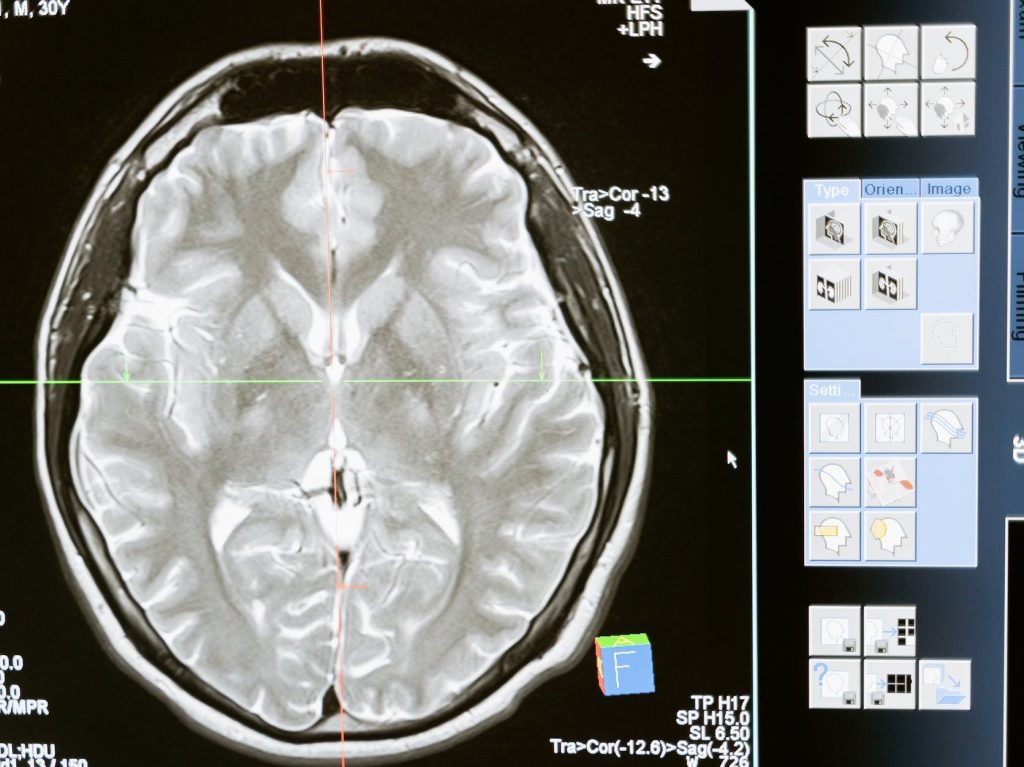

Cranıal mrı ınterpretatıon

Intermediate

Formal, informal, applied education on Cranial MRI interpretation during the Radiology clerkship, and Neurology clerkships and internships at the IUE Medical Point hospital.

Informal training on Cranial MRI analysis (with special focus on structural changes during healthy aging and dementia) during time spent as Independent Researcher in the Yener Lab.